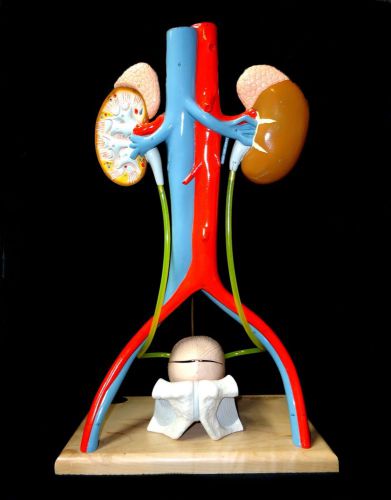

Denoyer Geppert - A55 Free-Standing Kidney Urinary System Anatomical Model base